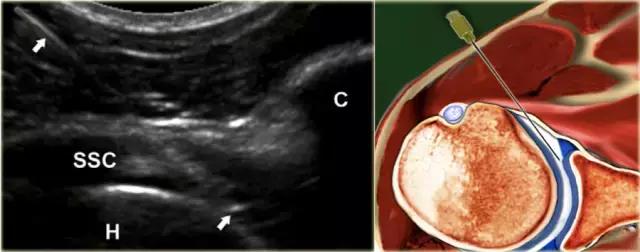

前路途径 在前路方法中,患者仰卧仰卧,伸出的手臂外旋(图)。超声探头在腹侧平行于肩胛腱的长轴放置。探头侧的灰线表示长轴。

使用22号针,针连接到包含造影剂的50mL注射器,由助手保持,在适当的针位置注射15-20mL造影剂时,针垂直于肱骨头的内侧边缘前进,穿透肩胛腱。

如果刺中肱骨头的软骨,针应该拉回1或2毫米,稍微倾斜大约15◦,然后前进切向与头部进入关节,针的斜面朝向关节(图) 。不应该感觉到注射阻力,并且应该看到对比剂自由进入关节并且存在于肩胛下凹部中。